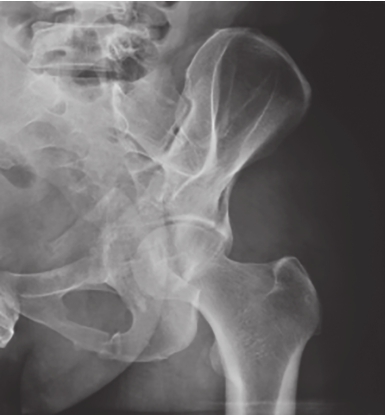

最为常用,患者仰卧,射线呈前后方向垂直投射,骨盆入口边缘与躯干纵轴呈45°~60°夹角。该位像基本能了解骨盆前后环骨折及骶髂关节骨折脱位情况。可用于鉴别骶骨、骨盆髋臼、近端股骨等部位骨折(图2-1)。

图2-1 骨盆前后位X线片

可见左侧骶髂关节骶骨及髂骨面局部骨质断裂,关节间隙增宽,左侧耻上、下支骨折,累及耻骨联合左侧缘。